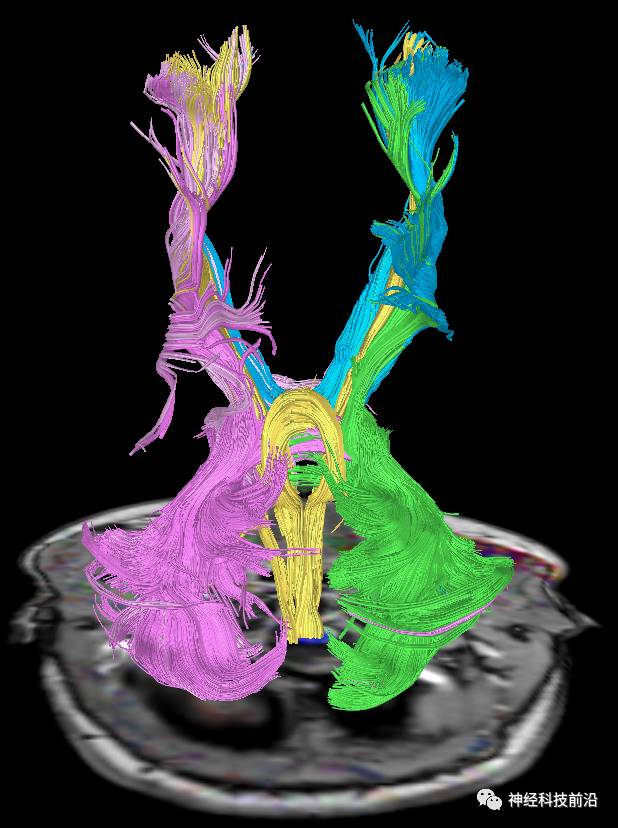

下面为皮质脊髓束的走形及位置

皮质脊髓束与皮质脑桥束的关系毗邻